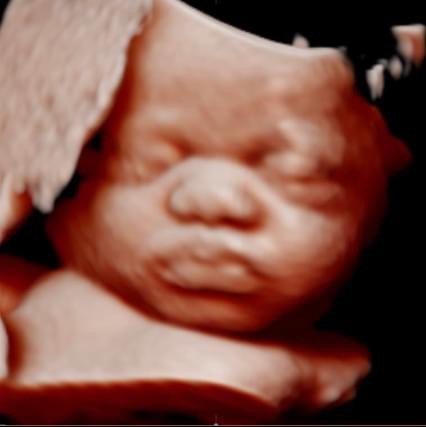

All photos are from our equipment and are of our actual clients.